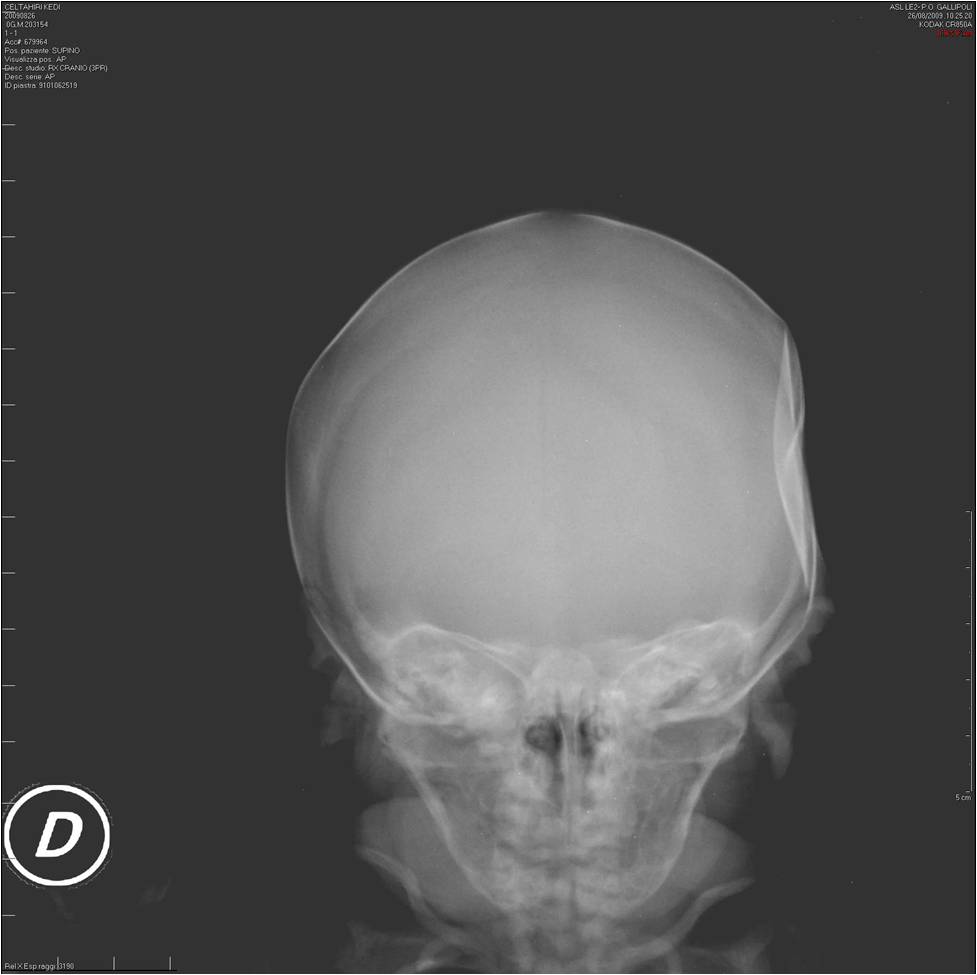

Descriviamo il caso di un neonato nato alla 36a settimana di gestazione (PN 2350 g) da parto cesareo per la presenza di gestosi materna (donna primigravida di 25 anni). Il neonato presentava alla nascita una depressione della teca cranica in sede temporale sinistra del diametro di 5 cm x 4 cm e della profondit� di circa 1,5 cm (Figura 1). Ha avuto un buon adattamento alla vita extra-uterina (Punteggio di Apgar 9-10 al primo e quinto minuto) con esame obiettivo generale e neurologico nella norma. � stata eseguita una radiografia del cranio (Figura 2) per escludere un�agenesia dell�osso temporale o una frattura dello stesso; l�ecografia transfontanellare era anch�essa normale. Al controllo clinico eseguito a due mesi dalla nascita, la depressione risultava scomparsa (Figura 3).

Figura 2.